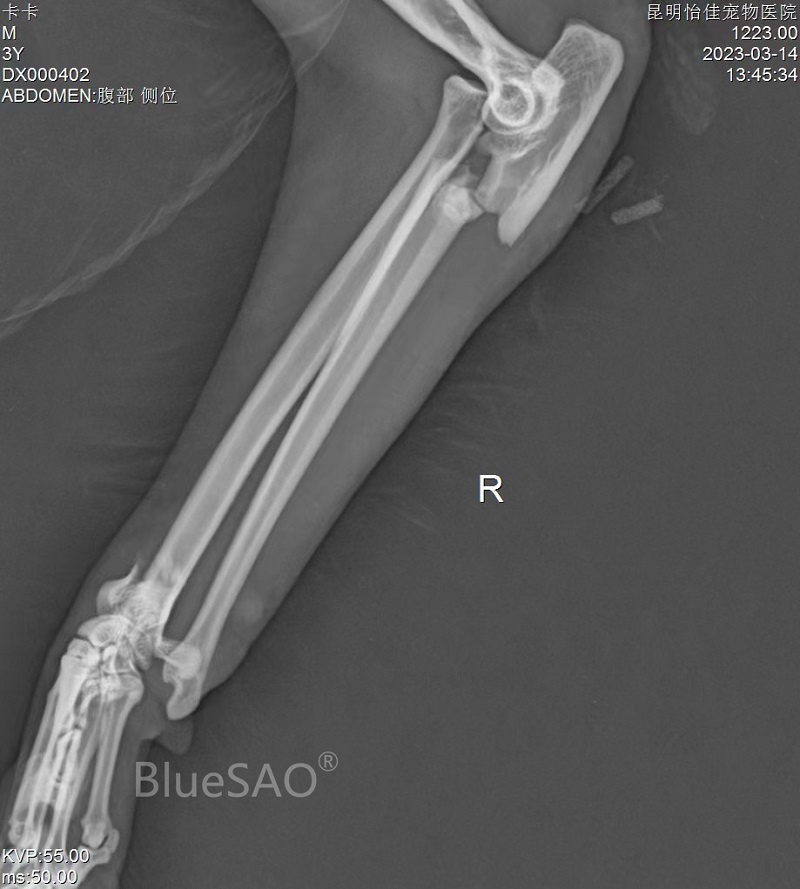

#猫# #36个月# #4.8kg# #桡骨-中段-粉碎性骨折# #尺骨-中段-粉碎性骨折# #掌骨-其它部位-其它类型#

布偶猫,昵称:卡卡,3岁,公,体重4.8Kg,因坠楼导致左侧桡尺骨中段粉碎性骨折、左侧掌骨骨折、右侧尺骨近端骨折、右侧桡尺骨远端骨折。术中桡尺骨采用BlueSAO佰陆PRCL ®6.5mm和5mm纯钛锁定骨板进行内固定,复位完好,康复良好。